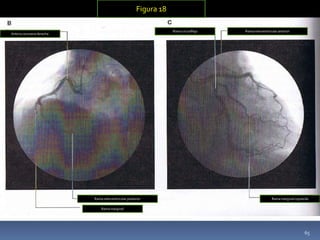

Figura 17. Arterias coronarias

1-Auricula derecha

2-Ventrículo derecho

3-Ventrículo izquierdo

4-Arteria coronaria derecha

5-Rama del nódulo sinoatrial

6-Rama marginal

7-Arteria coronaria izquierda

8-Rama circunfleja

9-Rama marginal izquierda

10-Rama interventricular anterior

11-Rama diagonal

12-Rama interventricular posterior

Figura 16

A-Vista anterior de la vasculatura

cardiaca

B-Vista superior de la vasculatura

cardiaca.

CORAZON

ARTERIAS

CORONARIAS

 Arteria coronaria derecha: Se origina desde el

seno aórtico derecho de la aorta ascendente,

cruza anteriormente y a la derecha entre la

AD y el tronco de la pulmonar y desciende

verticalmente por el surco coronario, entre la

AD y el VD, alcanza el borde cardíaco inferior,

donde se hace posterior y continua en el surco

coronario hasta la superficie diafragmática y la

base del corazón, emitiendo muchas ramas.

[Ver figura17]

 Arteria coronaria izquierda: Se origina

desde el seno aórtico izquierdo de la aorta

ascendente, cruza anteriormente y a la

izquierda entre la el tronco de la

pulmonar y la AI, desciende verticalmente

por el surco coronario, mientras

permanece posterior, se divide en dos

ramas terminales, la arteria

interventricular anterior (descendente

anterior izq.) y la arteria circunfleja.

[Ver figura 18]

Arteria coronaria derecha

Rama interventricular posterior

Rama marginal

Rama circunfleja Rama interventricular anterior

Rama marginal izquierda

Figura 18